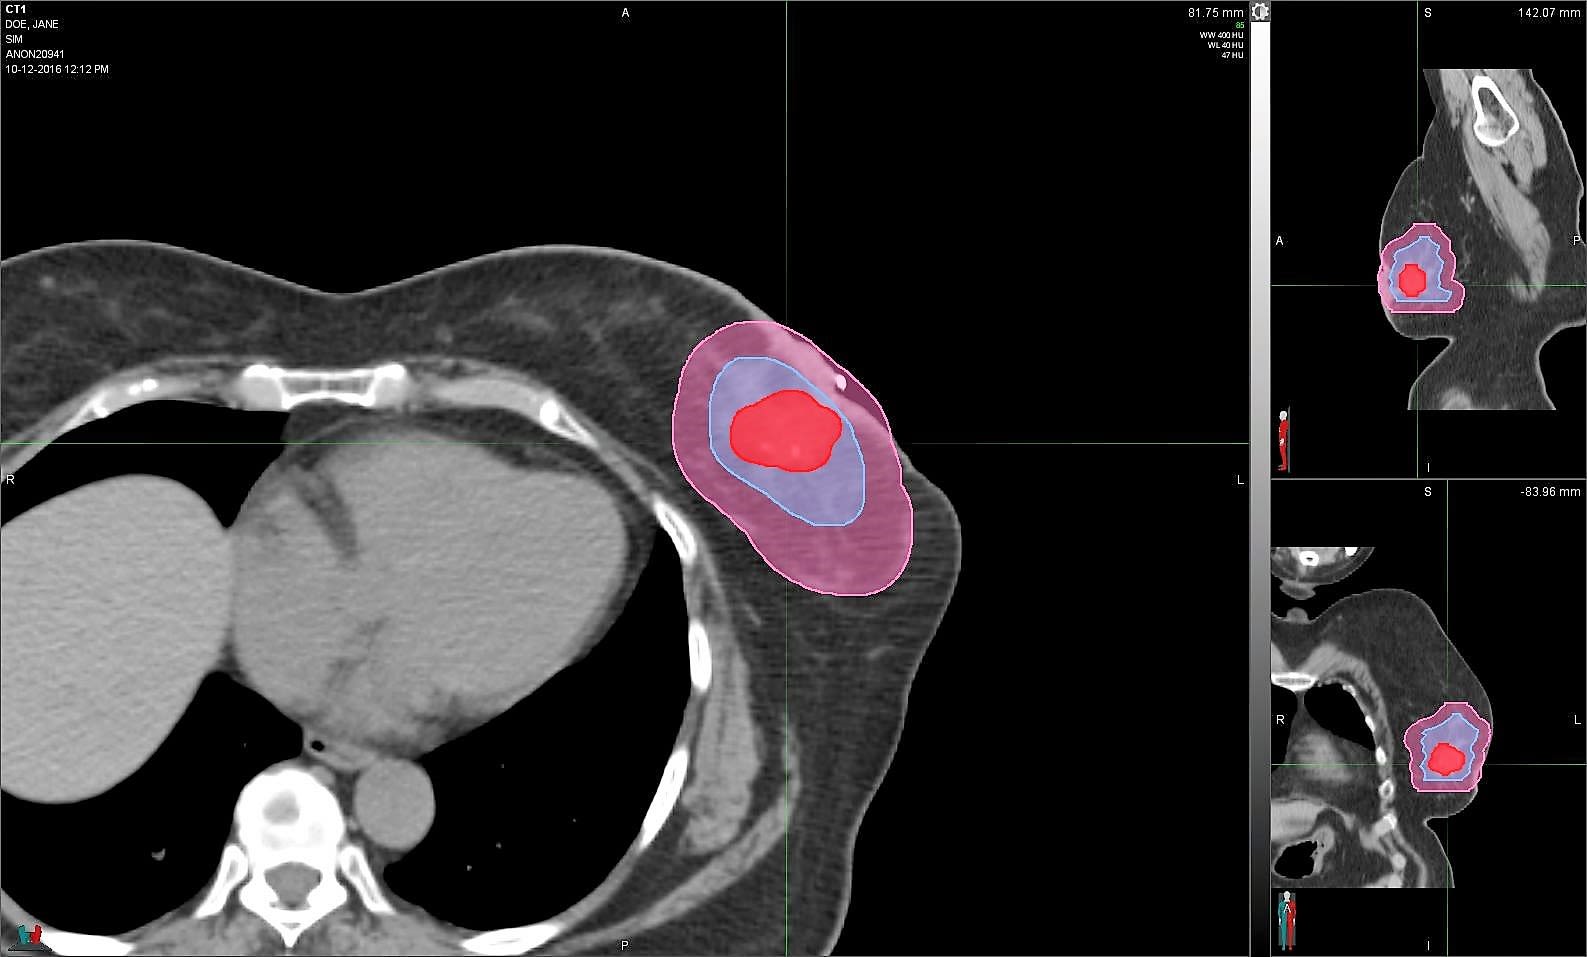

The colored portions of the scan represent the calculated area that gets radiated after breast conservation or lumpectomy. (Photos courtesy of Beth Anglin)